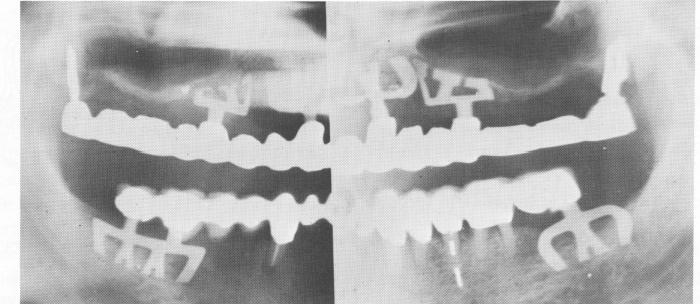

Fig. 11-206. The single tooth blades in the maxillae help stabilize anterior periodontally involved teeth. Some of these blades are obliquely set to avoid the maxillary sinus. In the mandible mesiodistal blades act as posterior abutments.